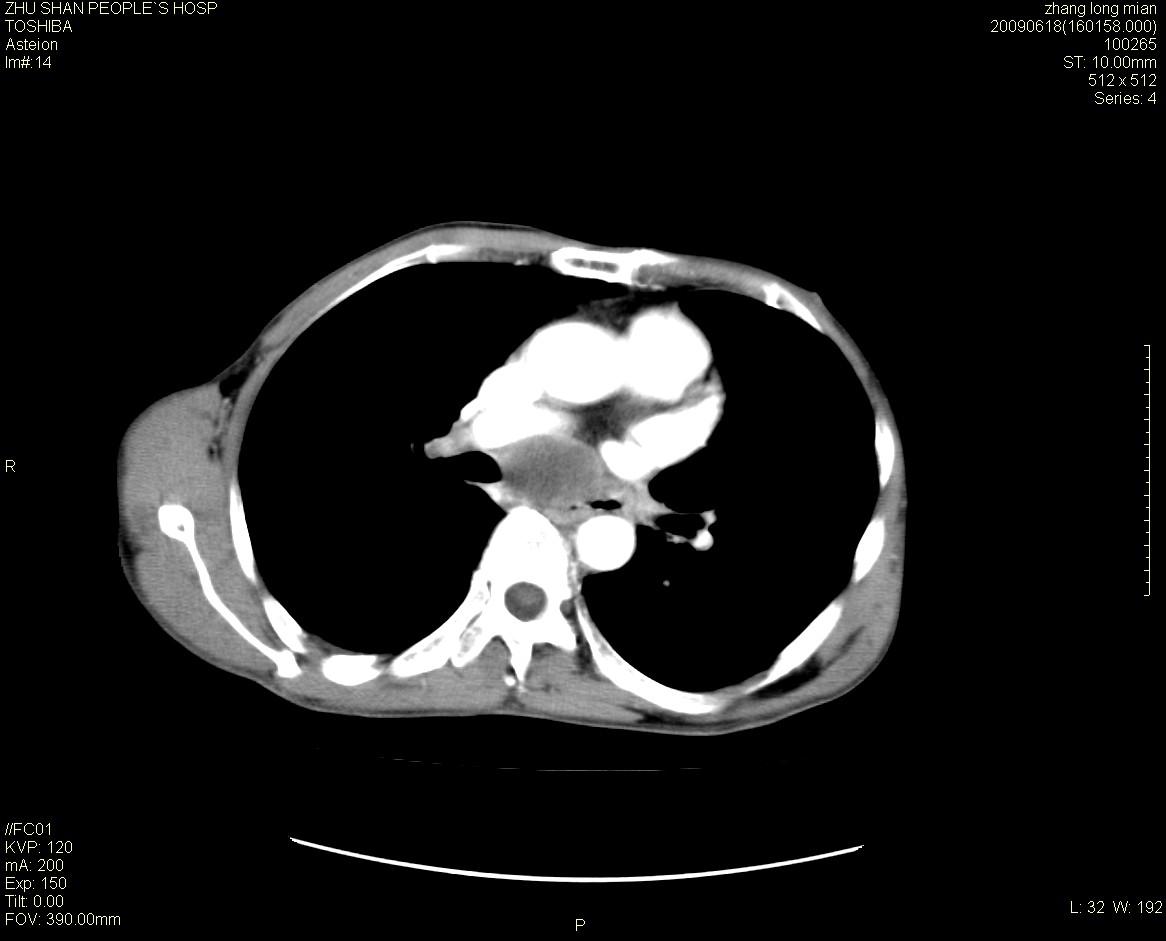

男性 65岁 胸片发现右下肺包块.诊断肺ca并纵隔转移没有问题吧!

肺ca并纵隔转移,阻塞性炎症。

两侧胸廓不对称,右侧呈塌陷改变,右肺萎缩。

右下肺见浅分叶状软组织块影,边缘有毛刺,其下部似见不完整偏心空洞影,邻近胸膜凹陷征,并胸腔积液。

增强见纵隔区气管隆突上下及左肺门区肿大淋巴结。左肺感染性病灶。

另见右上肺见一枚小结节影,性质待定。